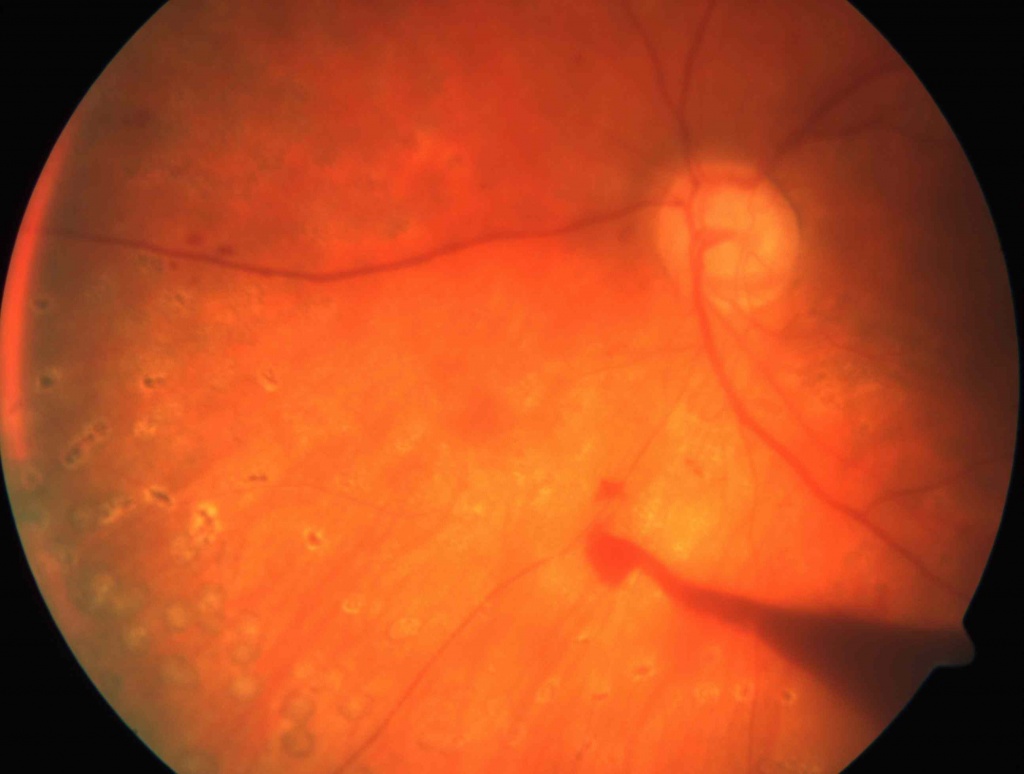

Гемофтальм -это кровоизлияние в стекловидное тело. Пациенты с гемофтальмом предъявляют жалобы на плавающие в поле зрения помутнения,«мушки», затуманивание зрения, появление паутины перед глазом. При тотальных гемофтальмах зрение снижается резко. Это может происходить при травмах, часто при сахарном диабете, гипертонии,заболеваниях крови, васкулитах. Иногда под гемофтальмом маскируется отслойка сетчатки. Частичные гемофтальмы могут рассасываться самостоятельно или при помощи рассасывающих препаратов. Тотальные кровоизлияния нуждаются в хирургическом лечении- витрэктомии. Любые кровоизлияния могут приводить к образованию спаек с сетчаткой и шварт, что в свою очередь вызывает отслойку сетчатки.

Отслойка сетчатки -патологическое состояние глаза,которое нуждается в срочном оперативном лечении, так как это заболевание приводит к достаточно быстрой полной потере зрения. Отслойки могут быть регматогенными- в результате образования разрыва сетчатки, как правило после трав и при близорукости; тракционными, возникающих после гемофтальмов и экссудативными при воспалительных заболеваниях и при опухолях сосудистой оболочки. Предвестниками отслойки сетчатки могут быть появление вспышек, искр, плавающих точек, что может указывать на образование разрыва сетчатки. Эти жалобы служат поводом для обращения к офтальмологу, так как на данном этапе возможно остановить развитие отслойки сетчатки при помощи лазеркоагуляции сетчатки. Далее появляются жалобы на снижение зрения и возникновение «занавески» перед глазом. Это признаки уже начавшейся отслойки сетчатки. Хирургическое лечение- единственный метод лечения при отслойке сетчатки. Витрэктомия - одно из самых сложных оперативных вмешательств в офтальмологии. Как правило, операции при отслойке сетчатки многоэтапные с применение вводимых в полость стекловидного тела перфтора и силиконового масла, одномоментной эндолазерлазеркоагуляцией. Реже выполняются эписклеральные операции.